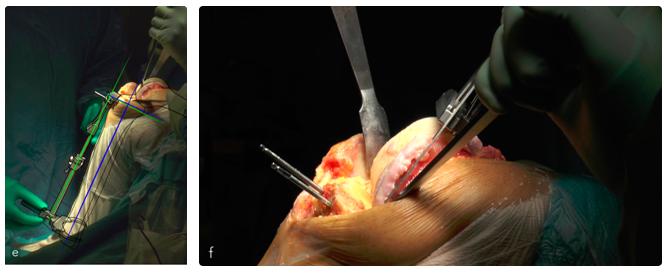

La tecnica chirurgica prevede diversi accessi scelti in base alle caratteristiche del ginocchio: accesso standard (47%) (d), sub-vastus (32%) e mid-vastus (18%) con artrotomia pararotulea mediale. In caso di gravi deformità in valgo è stato eseguito un acceso chirurgico standard con artrotomia pararotulea laterale (3%). L'impianto della protesi è guidato da un apposito strumentario che permette delle resezioni ossee precise per la correzione delle deformità assiali (e) e per l'impianto della protesi (f).